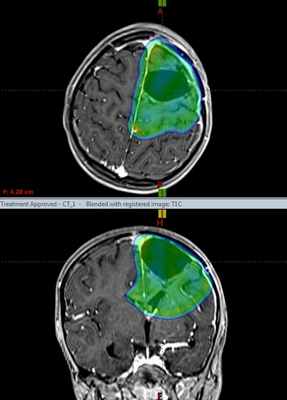

Протонная терапия, план лечения астробластомы. Зона, указанная синим и зеленым цветом, получит высокую дозу ионизируюшего излучения, гибельного для опухоли. Остальной мозг – защищен от радиации благодаря точности метода протонной терапии и высокой квалификации врачей МИБС.

Екатерина Бычковская болеет с начала 2018 года. При обследовании по данным МРТ выявлена опухоль мозга в левой лобной доле диаметром 6,5 см. После хирургического удаления был проведен гистологический анализ, заключение – Астробластома, Grade IV.

Учитывая гистологический диагноз, возраст пациента, выполненную резекцию опухоли, рекомендовано проведение лучевой терапии на область опухоли и параллельно – химиотерапии. Ввиду юного возраста и локализации опухоли предпочтительным методом лучевой терапии является протонная терапия.

В МИБС девочке проведен курс лучевой протонной терапии на ложе удалённой опухоли с применением установки Pro Beam. В конце апреля пациентка выписана для проведения следующего этапа лечения астробластомы, дома, в Республике Беларусь.